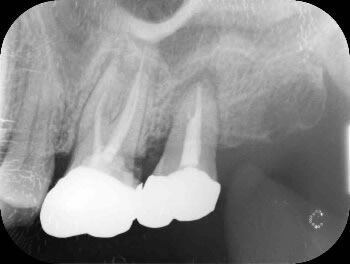

治療後のレントゲン写真にて、移植歯の周りに骨ができており、移植が問題なく成功していることがわかります。

その後は定期健診をしてメインテナンスをしていきます。